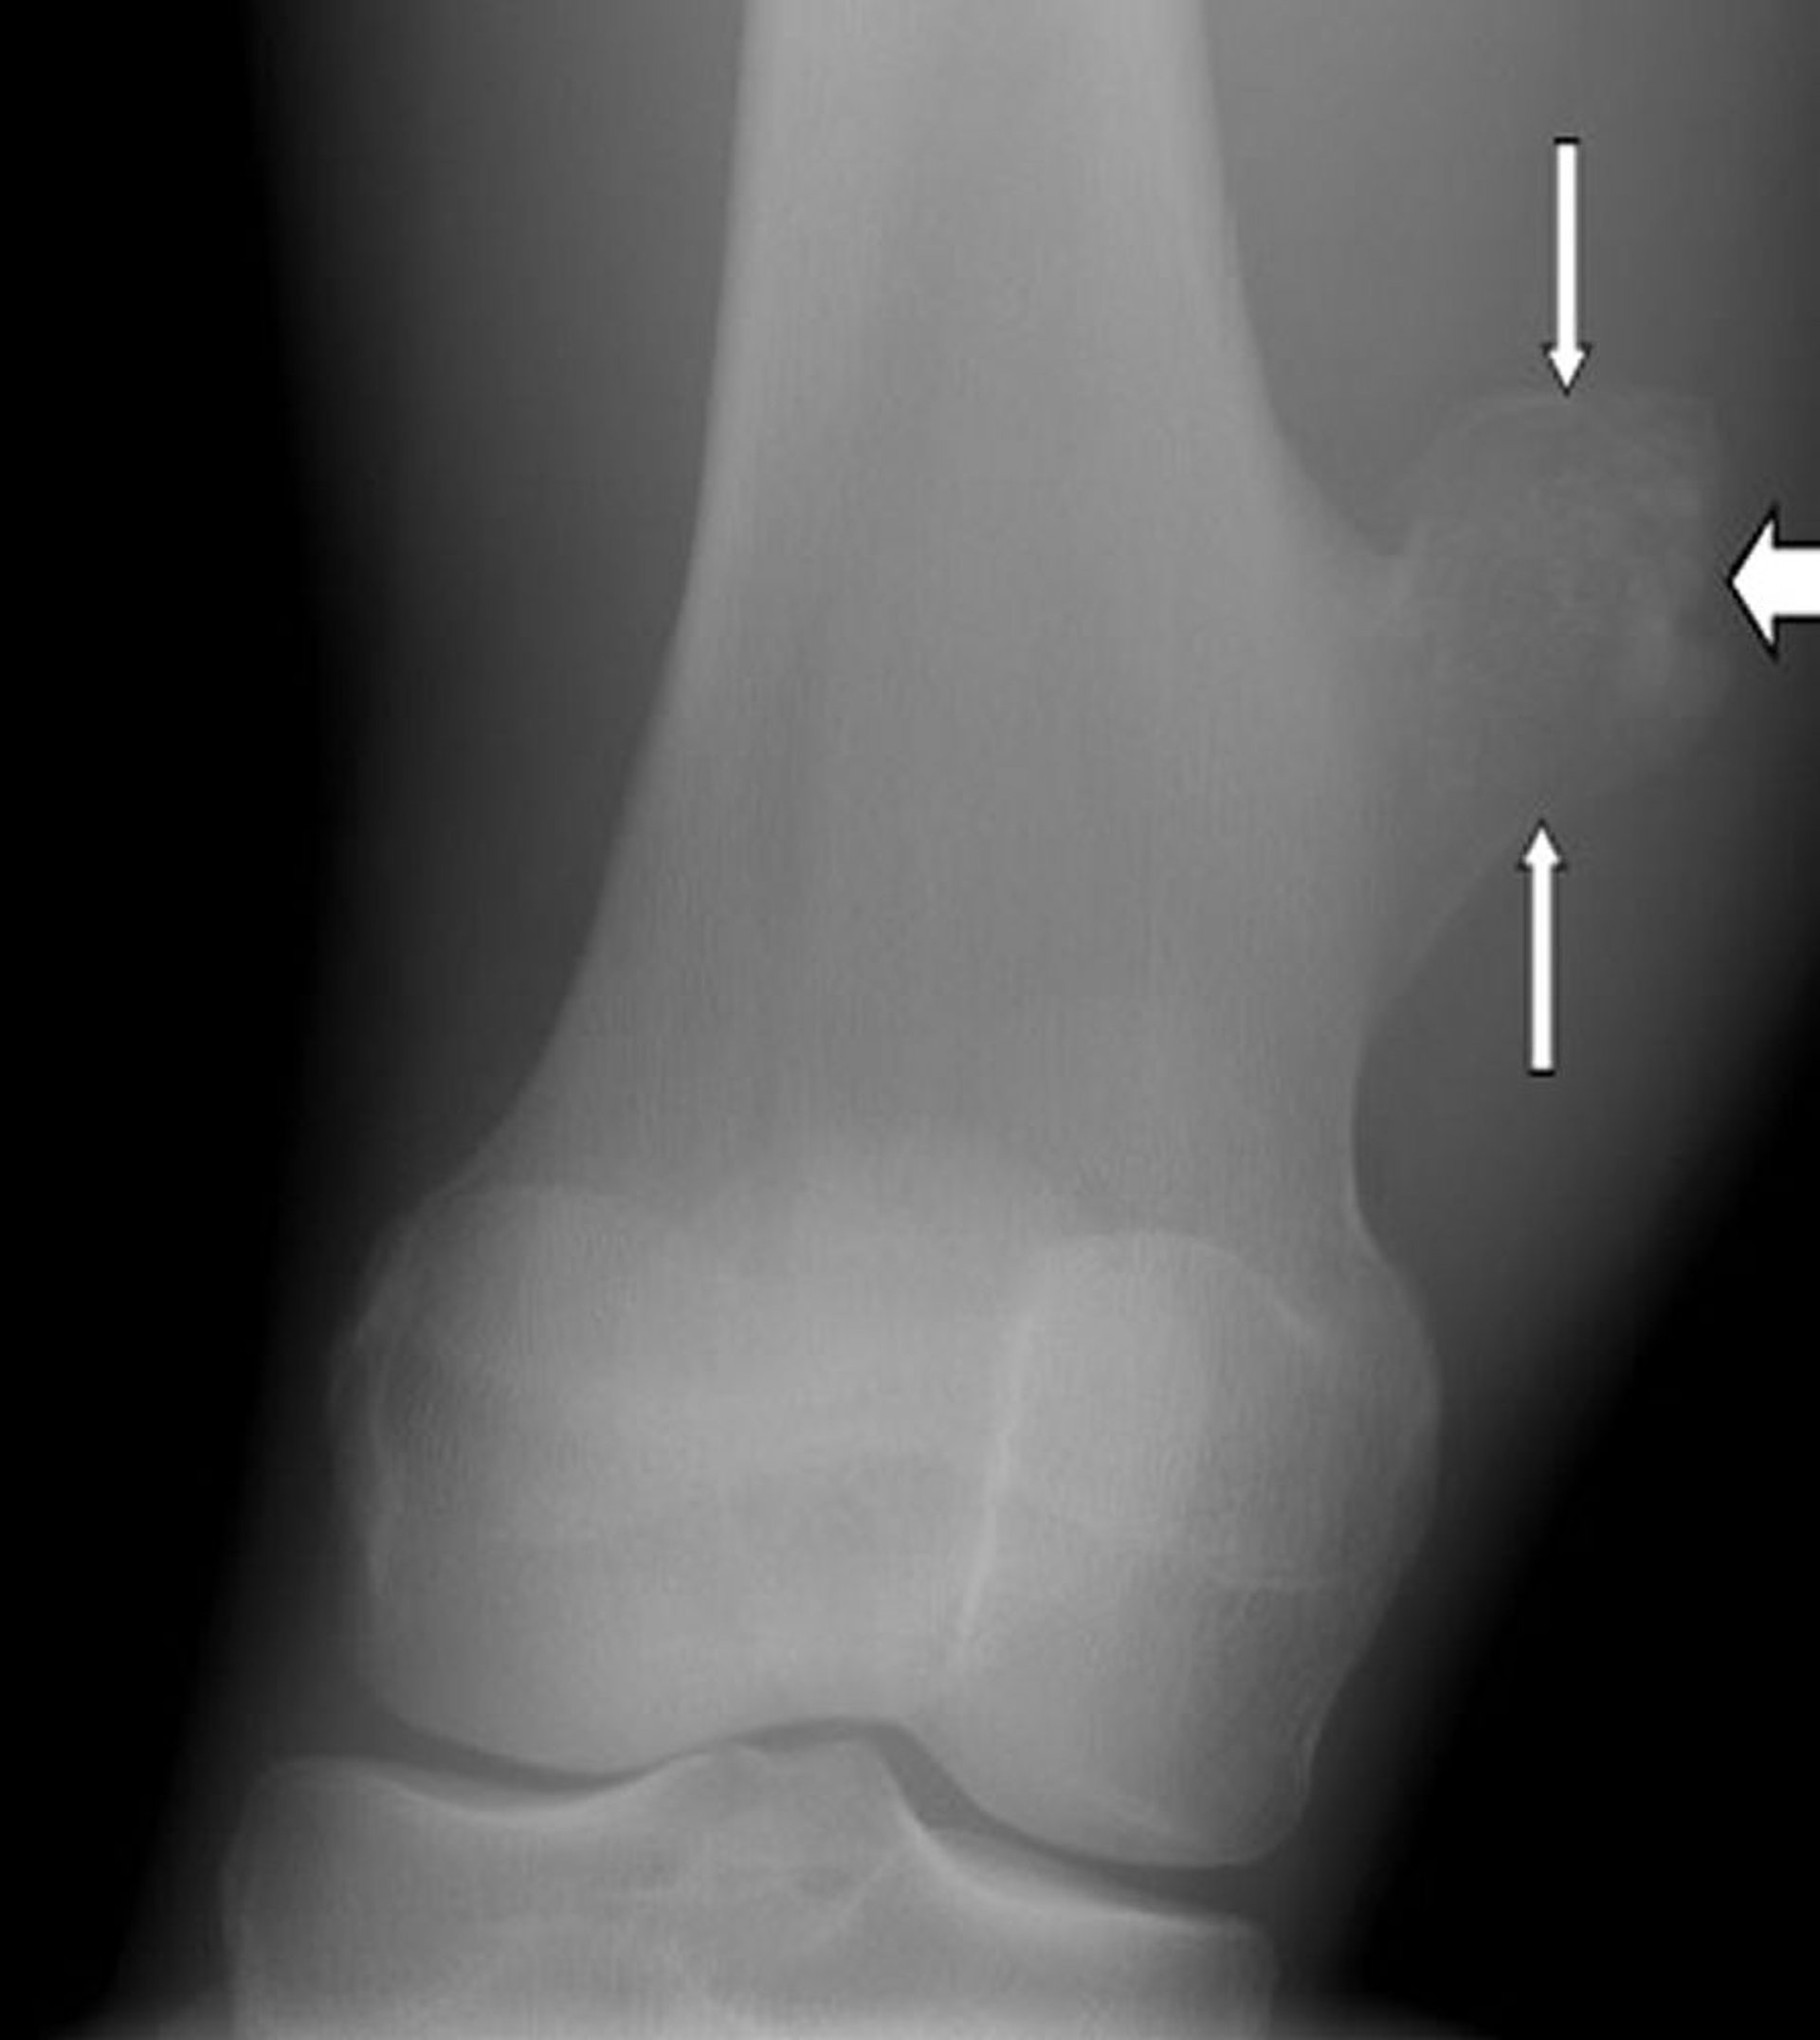

Остеохондрома колена

На этой рентгенограмме колена показана остеохондрома в виде новообразования на поверхности бедренной кости (стрелки) выше коленного сустава.

Изображение любезно предоставлено д-ром Майклом Дж. Джойсом (Michael J. Joyce) и д-ром Хаканом Иласланом (Hakan Ilaslan).